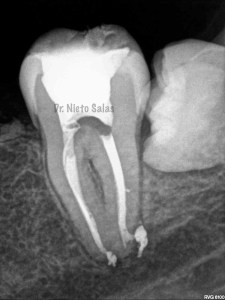

Bueno , ante esta piezas, que presentan una periodontitis apical crónica en la 4.7 y una pulpitis irreversible en la 3.7 nos disponemos a realizar le tratamiento de conductos.

Intentamos mantener la permeabilidad y la forma de  los conductos. Instrumentamos con Pathfile y Mtwo hasta un 25-6%.

(ORTO)                                                               (DISTO)